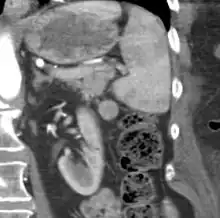

Gross pathology of an accessory spleen